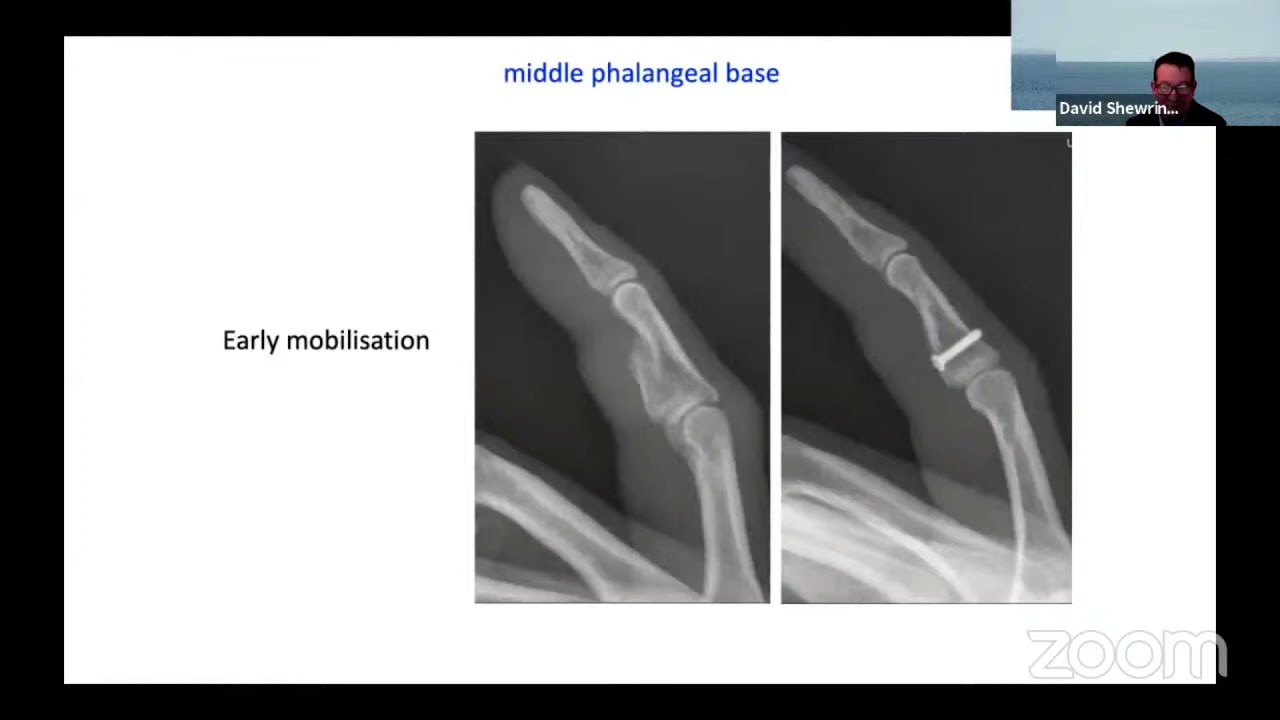

PIP Joint Dorsal Fracture Dislocation ORIF Through a Volar Approach